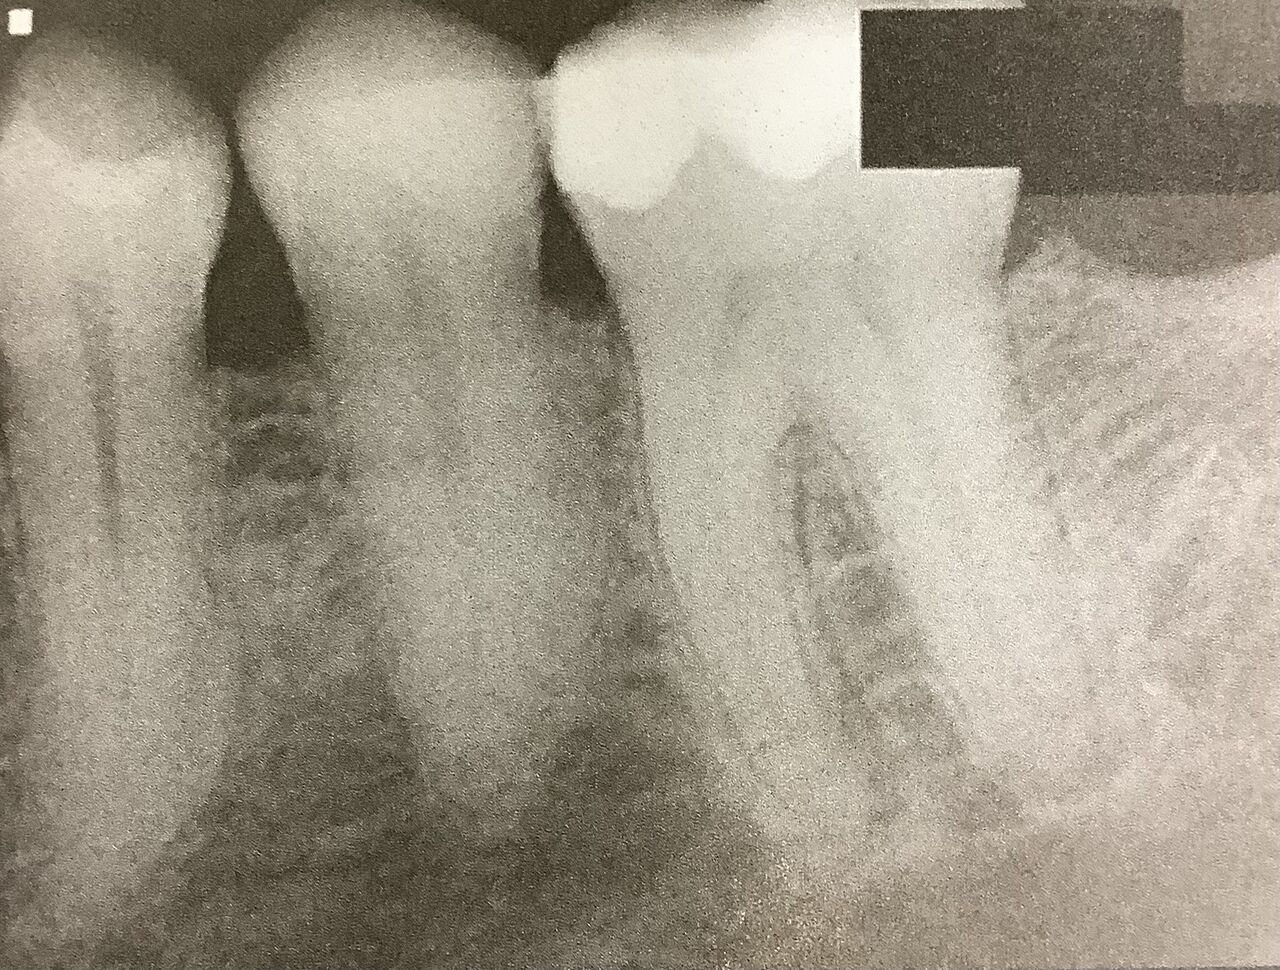

口の中には、痛みの原因となるようなものは見つかりません。

最近に根管治療をした6番も、押しても何ともありません。